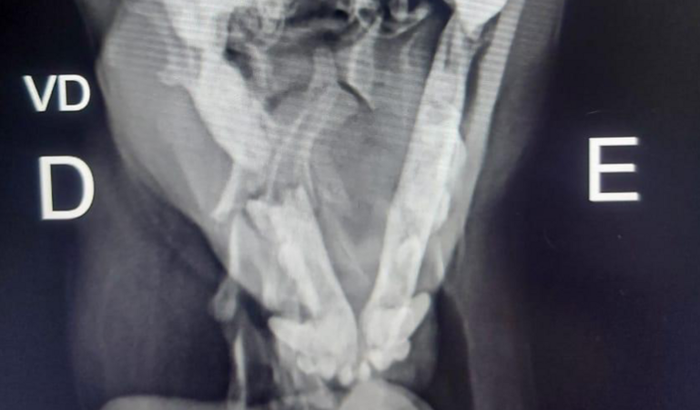

Gente meu cachorro quebrou o maxilar lado esquerdo e precisa de cirurgia urgente pois não consegue se alimentar .